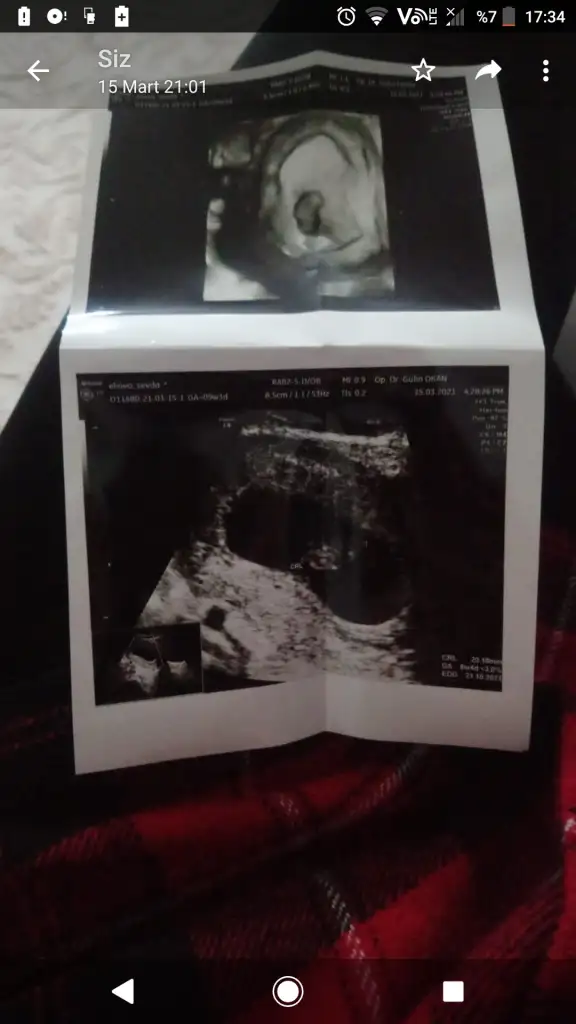

Ramzi teorisi okudum yüzde 97 dogruymuş.Ama neye göre bakcam ultrasona bilemedim. Size sormak istedim Bebeğim sağa daha yakın sanki bası da solda ayakları sağa bakıyor yani. Anlamadım ben. Sağlıklı olsun tabi kız erkek fark etmez ama merak ettim. İlk foto 5+5 iken 2.foto 9+3ken

Benim içinde bı tahminde bulunabilir misiniz ultrason görüntüsü vajinal karından değil ona göre de değişiklik gosteriyomus yaÇok sagol 9+6yız bugün bakalım kısmet. Sağlıklı olsun da

Eger sol alttaki golge bebek ise kiz benceBenim içinde bı tahminde bulunabilir misiniz ultrason görüntüsü vajinal karından değil ona göre de değişiklik gosteriyomus ya

Banada bakarmısınız acaba rica etsemEger sol alttaki golge bebek ise kiz bence

Tabiki 7 8 haftalik ultrason kagidi varsa at alttan mi ustten mi soyle tahmin yapayim canimBanada bakarmısınız acaba rica etsem